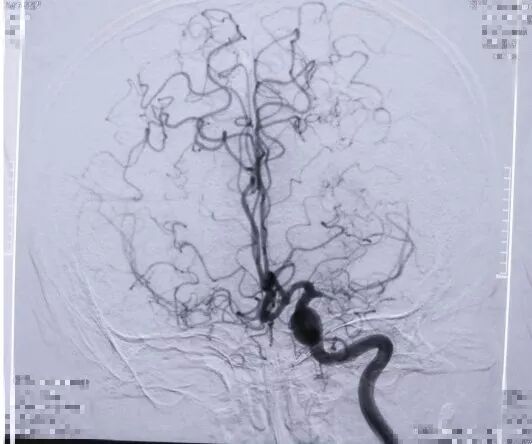

2017.04 DSA L-ICA